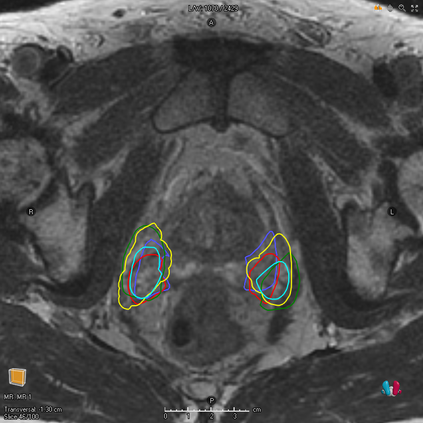

We study two of the most popular performance metrics in medical image segmentation, Accuracy and Dice, when the target labels are noisy. For both metrics, several statements related to characterization and volume properties of the set of optimal segmentations are proved, and associated experiments are provided. Our main insights are: (i) the volume of the solutions to both metrics may deviate significantly from the expected volume of the target, (ii) the volume of a solution to Accuracy is always less than or equal to the volume of a solution to Dice and (iii) the optimal solutions to both of these metrics coincide when the set of feasible segmentations is constrained to the set of segmentations with the volume equal to the expected volume of the target.